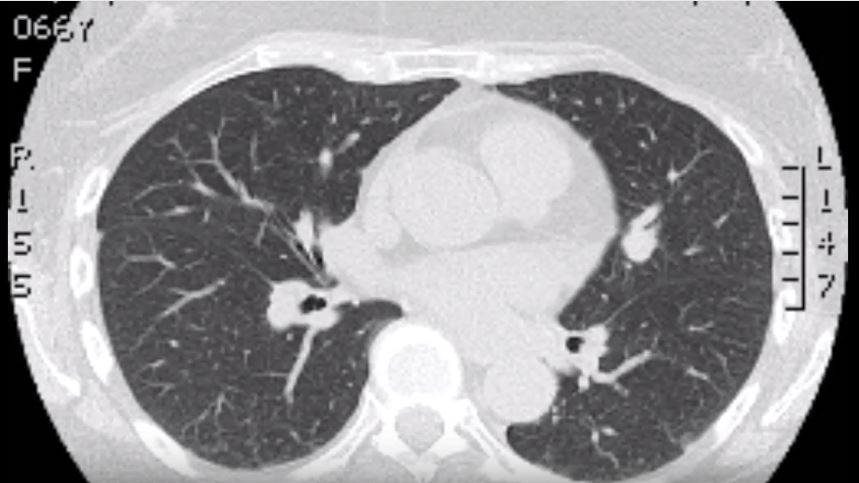

Atrial Septal Defect Closure in the Setting of Severe Pectus Excavatum: A Unique Case

The Ravitch Procedure With External Rib Plating to Maximize Relief of Cardiac Compression